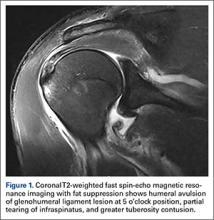

Standard shoulder radiographs showed no bony abnormalities and a concentrically reduced glenohumeral joint. Magnetic resonance imaging (MRI), reviewed by a staff musculoskeletal radiologist and a sports fellowship–trained orthopedic surgeon, showed a greater tuberosity contusion, a partial tear of the infraspinatus, and a HAGL lesion (Figure 1).